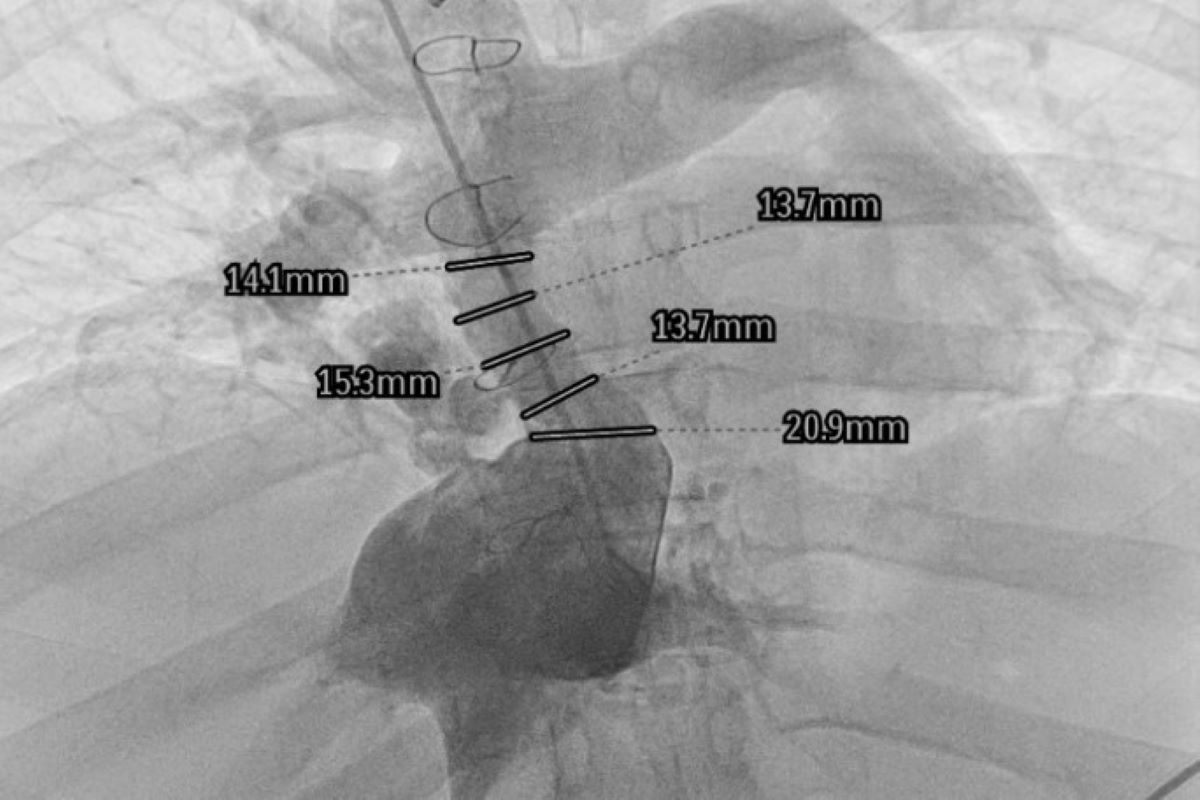

Chest X-ray showing the Fontan tunnel and metal surgical staples.

For the first time, the WUM University Clinical Center has conducted a procedure of broadening the Fontan tunnel in an adult patient using vascular access.